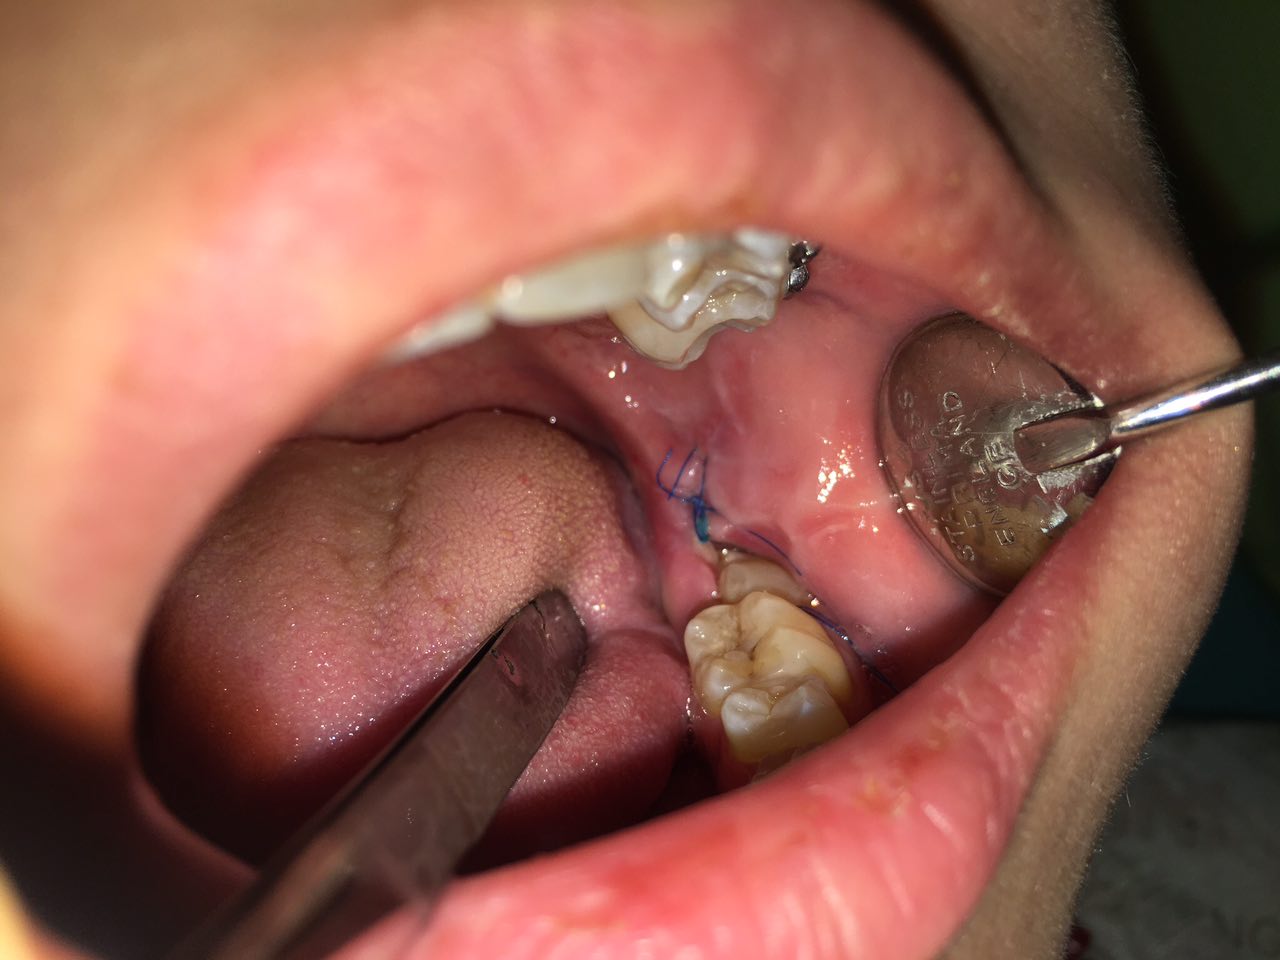

Воспаление после удаления зуба мудрости фото

Заживление Зуба Мудрости Фото – Telegraph

Удалили Зуб Мудрости Фото — Bluemorphotours.ru